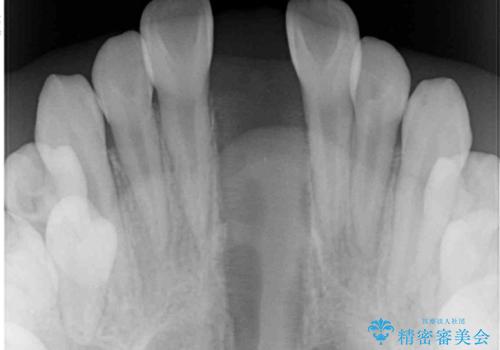

- 小児矯正の頃から診察を行っている患者様です。

上顎骨の幅が下顎骨よりも小さいので、拡大装置により骨幅を広げて上下関係を改善し、その後インビザラインにて歯並びを整えることとしました。